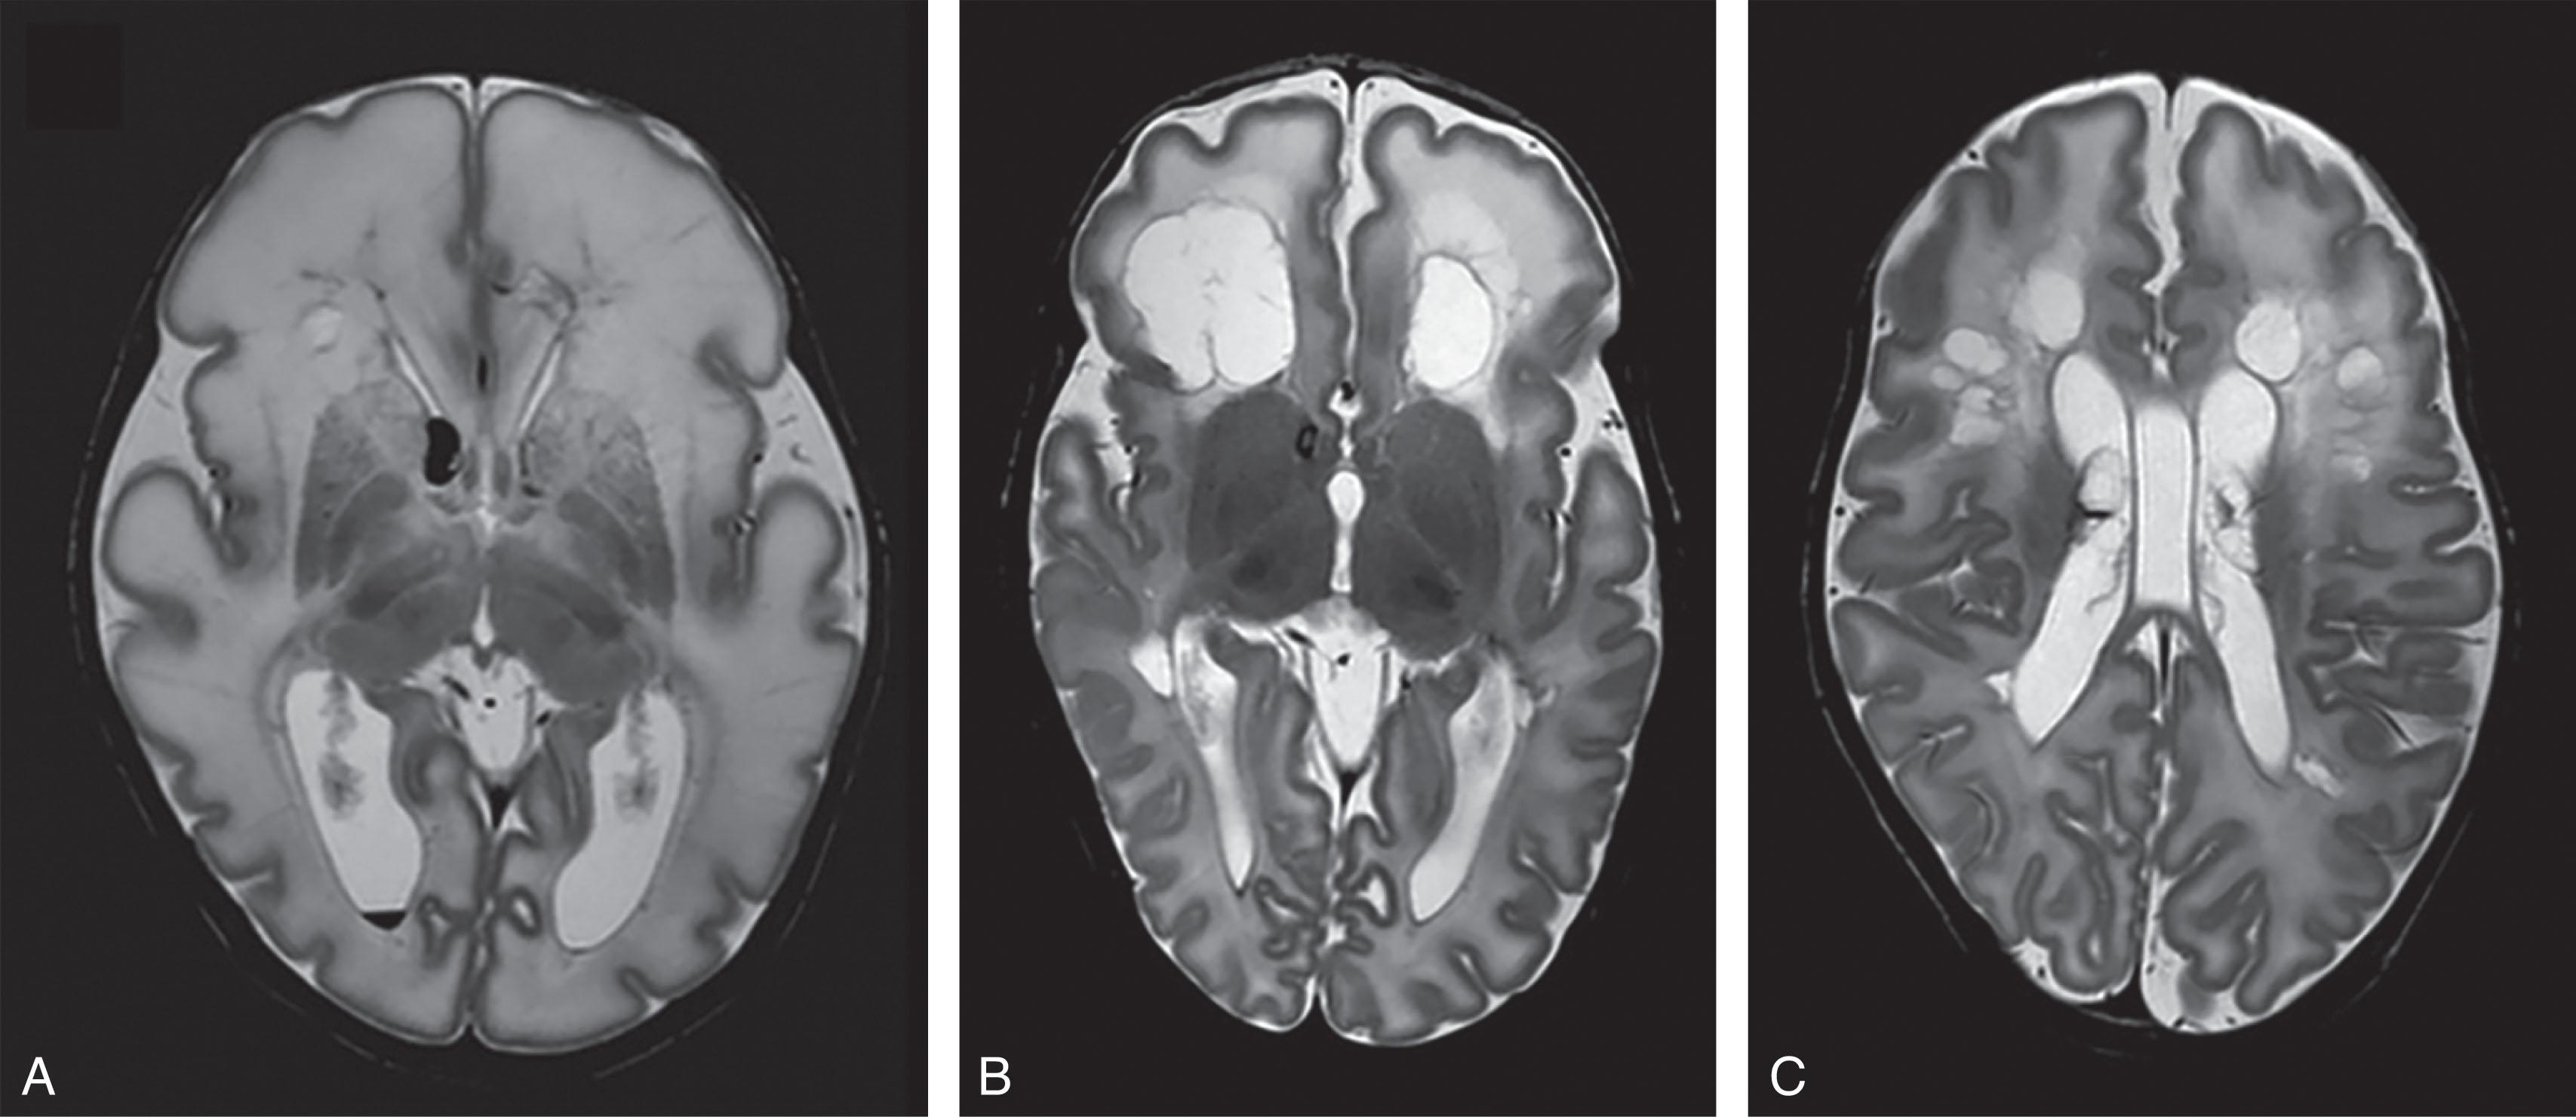

Fig. 20.2, Spectrum of WMI with severe (A & D), moderate (B & E) and mild (C & F) represented by schematics (A–C) with related magnetic resonance images (D–F).

The hallmark of the encephalopathy of prematurity is cerebral WMI (see Chapter 18 ). To understand the value and the challenges of neuroimaging of the encephalopathy in the neonatal period, we should review briefly the neuropathology of WMI. WMI consists of two distinct components: focal necrosis , with loss of all cellular elements, dorsal and lateral to the lateral ventricles, and a more cell-specific diffuse injury involving pre-OLs in cerebral white matter and marked by astrogliosis and microgliosis. A spectrum of severity is recognized and in living infants is based on neuroimaging (principally MRI). Thus WMI can be categorized into three subtypes ( Table 20.5 ). The most severe form involves focal necroses that are macroscopic in size (i.e., relatively large, more than several millimeters) and evolve to tissue dissolution and cystic change over a period of weeks. This focal necrotic/cystic form is often simply termed cystic PVL or cystic WMI (see Fig. 20.1 ) and is readily detected by cranial ultrasonography or MRI (see later, Fig. 20.11 ). Cystic PVL/WMI is now uncommon and has an overall incidence in living VLBW infants of 3% or less. Recent data from the Vermont Oxford network on >40,000 preterm infants with a birthweight of <1500 g showed that the incidence of cystic WMI was static from 2014 to 2021 at 2.7% to 2.8%, with the highest rates of occurrence in the preterm infants weighing <750 g at 4% to 5% (see Fig. 20.6 ).

In the largest neuropathological series of preterm infants ( n = 41), approximately 40% exhibited PVL with focal necroses, but macroscopic necroses were observed in only 18% of these PVL cases (only 7% of the total of autopsied preterm infants). A moderate form of WMI involves focal necrotic lesions that are 1 to 2 mm in size and, upon tissue dissolution, evolve not to cysts but rather to focal glial scars, sometimes visible as punctate areas of increased signal intensity on T 1 -weighted MRI ( Fig. 20.7 ). This form, often termed noncystic or punctate WMI , occurs in approximately 25% of living infants. Finally, the least severe form of PVL involves a focal necrotic component <1 mm in size; that is, microscopic and so small as to be invisible to neuroimaging. This mild form, like all forms of WMI, exhibits the diffuse gliosis neuropathologically as described in Chapter 18 . The degree of the diffuse abnormality generally correlates with the severity of WMI (see Table 20.5 ). The MRI correlate of the diffuse gliosis likely is the diffuse signal change described later. The mild form of PVL is likely present in a substantial minority of premature infants (see later). In the neuropathological series just noted, fully 82% of neuropathologically defined PVL cases (34% of the total series of autopsied premature infants) had focal necrotic lesions that were <1 mm and therefore likely below the detection of conventional clinical MRI scanners. Such cases may fail to be classified as WMI by MRI. In addition, the timing of the MRI may be crucial in recognition of WMI (see later), in that term equivalent MRI may fail to detect as much as 30% of all WMI in the preterm infant. All three subtypes of WMI include the diffuse component, characterized by astrogliosis/microgliosis and, after the initial pre-OL cell death, an excess of oligodendroglial progenitors. These oligodendroglial progenitors, however, fail to differentiate into myelin-producing cells (see Chapters 18 and 19 ). The severity of the diffuse component appears to parallel the severity of the PVL.